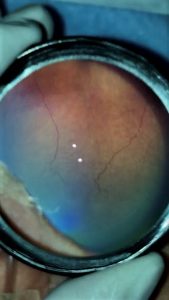

Vascularización incompleta